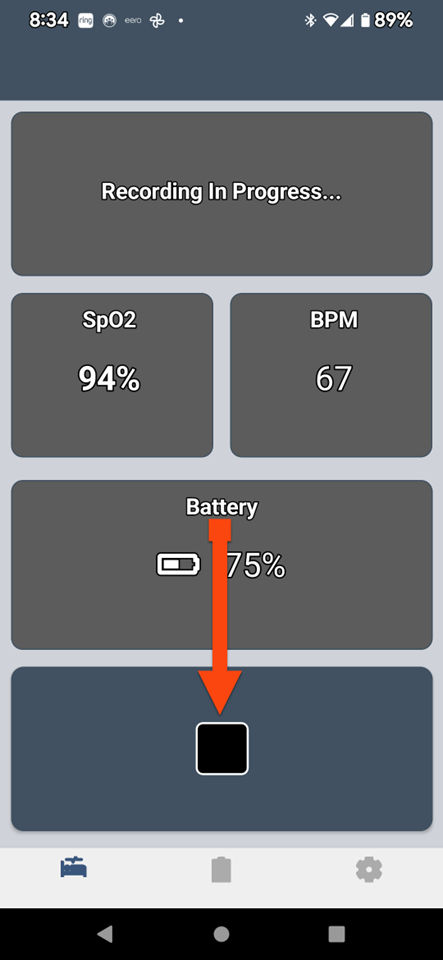

SLEEPIMAGE APP (Android)

SLEEPIMAGE APP (Android)

SLEEPIMAGE APP (Android)

SLEEPIMAGE APP (Android)

SLEEPIMAGE APP (Android)

SLEEPIMAGE APP (Android)

SLEEPIMAGE APP (Android)

SLEEPIMAGE APP (Android)

SLEEPIMAGE APP (Android)

SLEEPIMAGE APP (Android)

SLEEPIMAGE APP (Android)

SLEEPIMAGE APP (Android)

SLEEPIMAGE APP (Android)

SLEEPIMAGE APP (Android)

SLEEPIMAGE APP (Android)

SLEEPIMAGE APP (Android)

SLEEPIMAGE APP (Android)

SLEEPIMAGE APP (Android)

SLEEPIMAGE APP (Android)

SLEEPIMAGE APP (Android)

SLEEPIMAGE APP (Android)

SLEEPIMAGE APP (Android)

SLEEPIMAGE APP (Android)

SLEEPIMAGE APP (Android)

SLEEPIMAGE APP (Android)

SLEEPIMAGE APP (Android)

SLEEPIMAGE APP (Android)

SLEEPIMAGE APP (Android)

SLEEPIMAGE APP (Android)